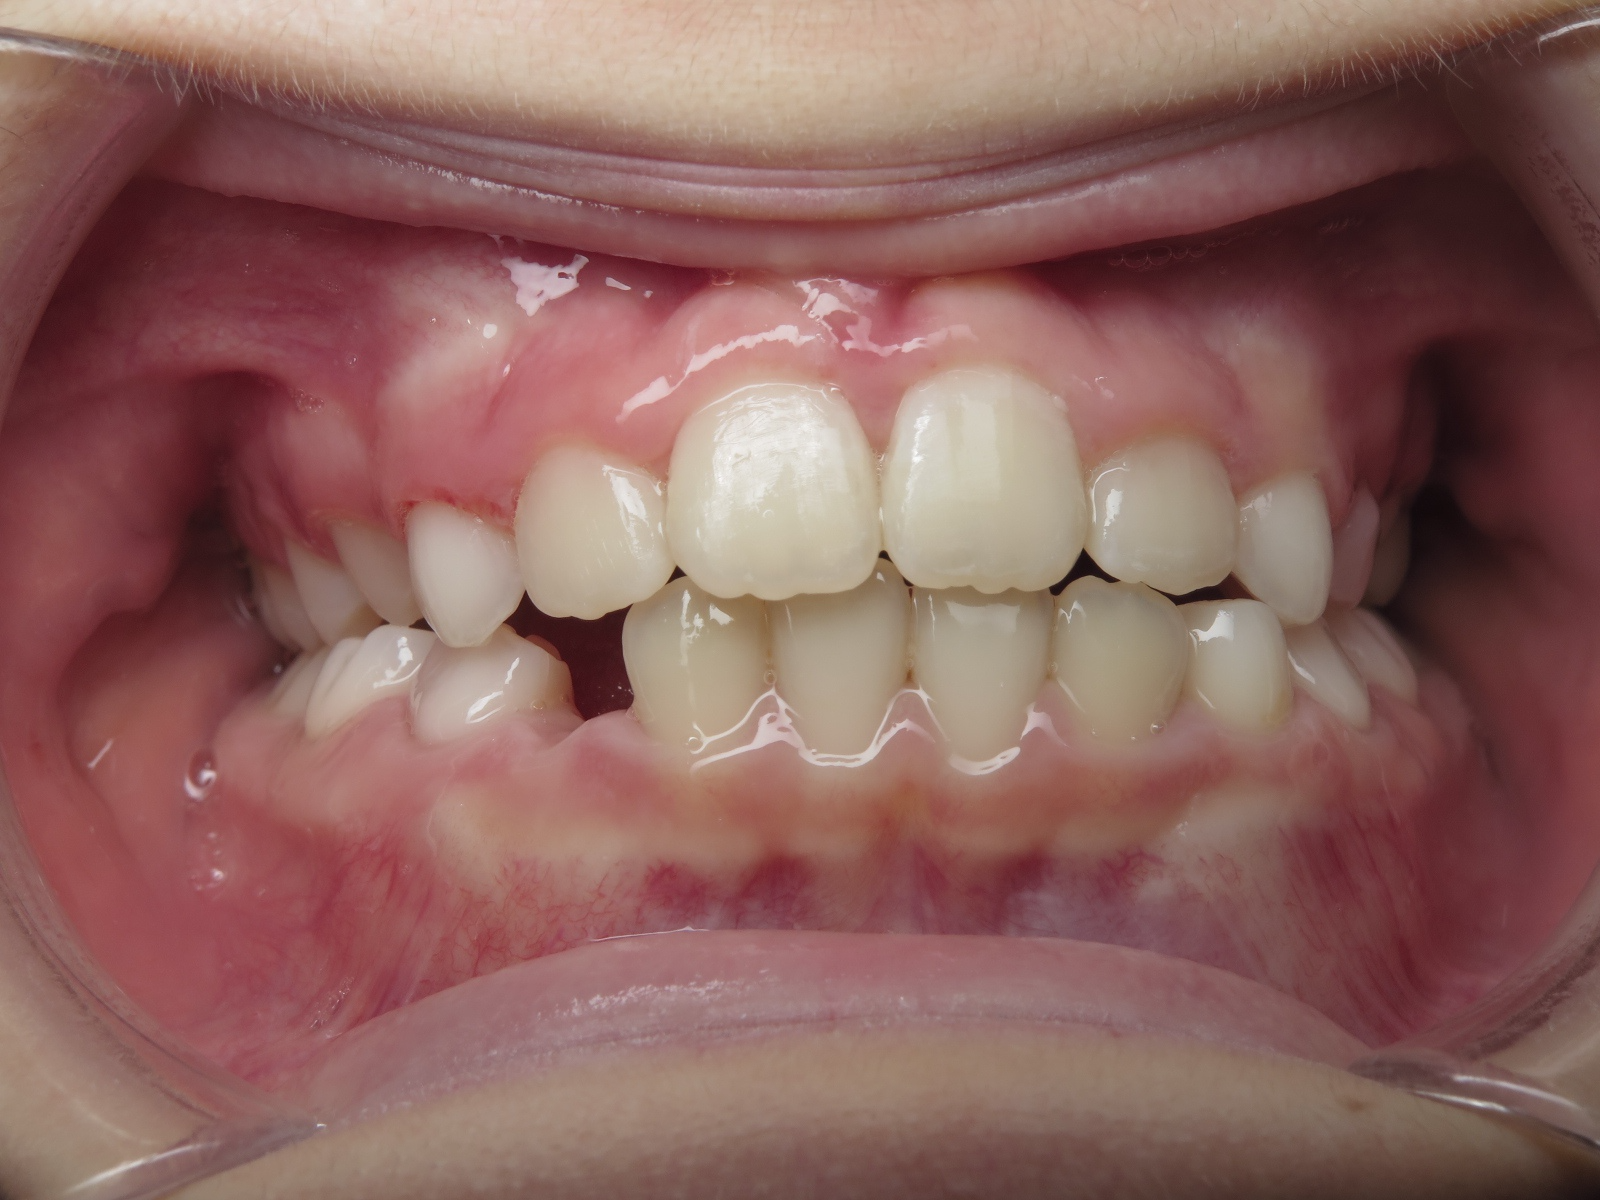

appareillage mobile pendant 22 mois

appareillage sectionnel multibagues pendant 18 mois

surveillance évolution de la dentition en cours